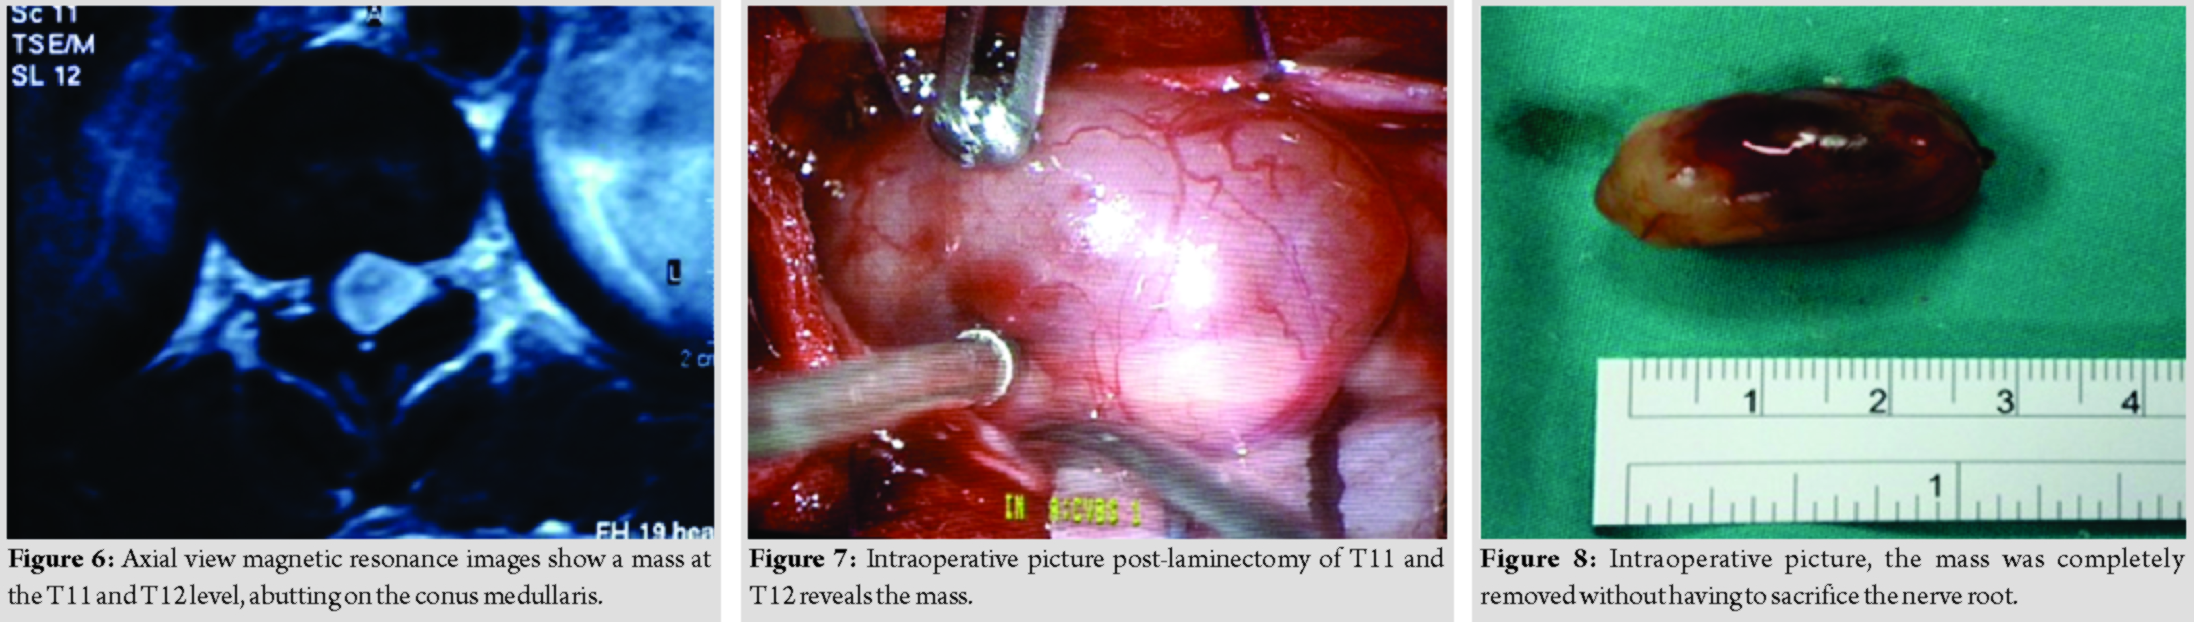

A 44-year-old lady presented with back pain and bilateral lower limb weakness for 2 years duration. She then progressed to develop urinary incontinence for 2 months duration. Clinical examination reveals bilateral lower limb hypertonia, lower limb power was Grade 0, and reflexes were brisk, sensory reduced from T11 dermatome onward. Magnetic resonance imaging reveals an intramedullary mass adjacent to the conus medullary (Fig. 5 and 6). Differential diagnosis at that point of time was astrocytoma and ependymoma. She underwent laminectomy of T11 and T12 with microscopic assisted tumor excision (Fig. 7 and 8). The mass was removed completely without having to sacrifice the involved nerve root. At 1-week post-operative, she was able to ambulate with aid. At 1-month post-operative, she was able to ambulate without aid, regained her bladder control and back pain resolved. Final histopathological findings reveal schwannoma.

A 53-year-old lady presented with complaint of back pain and bilateral lower limb weakness for a year duration, associated with urinary incontinence for 2 months duration. Examination reveals normal tone, power over the right lower limb was more affected (MRC Grade 2) as compared to the left lower limb (MRC Grade 3), lower limb reflexes were brisk, and sensation was reduced from T11 dermatome onward. Magnetic resonance imaging reveals a well-defined intradural extramedullary mass at T11, compressing on the conus medullaris (Fig. 9 and 10).

She underwent laminectomy of T10 and T11 with microscopic assisted excision of the tumor. The mass was successfully removed completely without sacrificing the involved nerve root (Fig. 11 and 12).